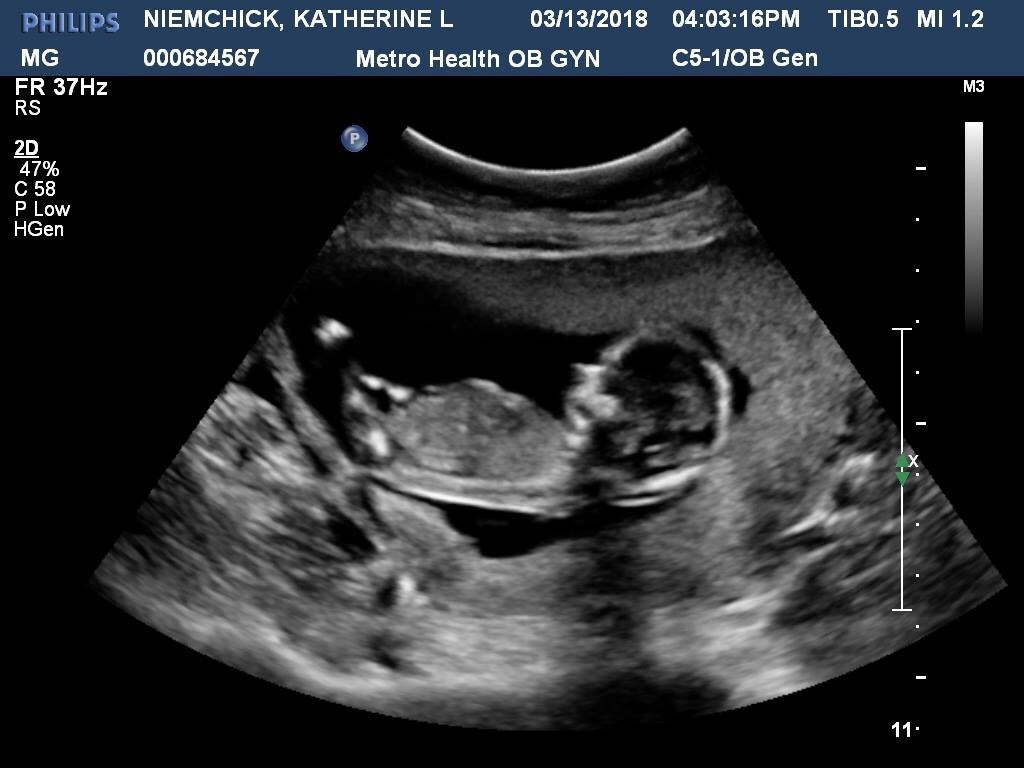

The ultrasound tech said she couldn’t see anything between the legs, but wouldn’t give a prediction. Can anyone tell? Thank you!!Attachment 38988Attachment 38989Attachment 38990

I can see a girl nub

I think girl! :)

Looks girly

girl lean for me to based on 2nd pic

It was confirmed a GIRL at our 20 week scan!!